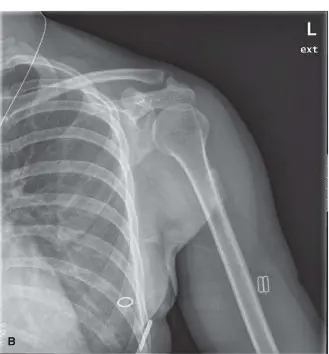

الأشعة السينية الأولية (X-ray Findings)

• الأشعة الأولية بعد الإصابة مباشرة: غالبًا ما تكون الأشعة السينية التي تُجرى بعد الإصابة الأولية مباشرة طبيعية تمامًا، ولا تُظهر أي إصابات عظمية حادة أو تكلسات في الأنسجة الرخوة.

• الأشعة السينية بعد 4-6 أسابيع: في هذه المرحلة، قد تبدأ الأشعة السينية في إظهار تكلسات خفيفة وغير محددة المعالم داخل الأنسجة الرخوة للعضلة. قد تكون هذه التكلسات غير منظمة في البداية.

• الأشعة السينية بعد 8-12 أسبوعًا وما بعدها: مع مرور الوقت ونضوج الآفة، تُظهر الأشعة السينية نمطًا أكثر تنظيمًا للتكلس. العلامة المميزة والتشخيصية لالتهاب العضلات المتكلس هي "ظاهرة المنطقة" (Zone Phenomenon). تعني هذه الظاهرة وجود حافة خارجية ناضجة وكثيفة من العظم تحيط بمركز أقل كثافة وأكثر شفافية للأشعة. من المهم ملاحظة عدم وجود تآكل في قشرة العظم المجاور أو تفاعل سمحاقي (نمو عظمي جديد من السمحاق)، وهي علامات قد تشير إلى ورم خبيث.

الأشعة السينية الأولية تظهر تكلسات مبكرة وغير محددة المعالم داخل العضلة الرباعية بعد حوالي 6 أسابيع من الصدمة.

الشكل 1: الأشعة السينية الأولية تظهر تكلسات مبكرة وغير محددة المعالم داخل العضلة الرباعية بعد حوالي 6 أسابيع من الصدمة.